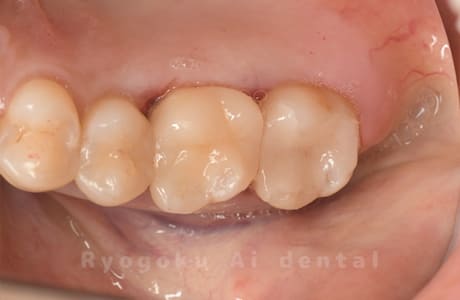

Case08

-

- 原因

- 虫歯

- 治療内容

- セラミックインレー

- 治療費用

- 77,000円

奥歯の黒い点が気になるということで来院された患者さんです。白い詰め物を外したところ、虫歯が中で大きく広がっていたため、患者さんと相談し、セラミックインレーで治療を行いました。

<リスク・副作用>

過度の咬合や衝撃で割れることがあります。